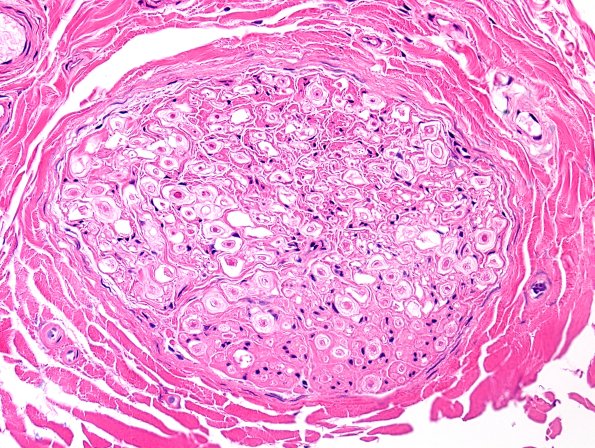

Washington University Experience | PERIPHERAL NEUROPATHY | 0 PNS ARTIFACTS | 17A Artifact, delayed fixation, sural nerve H&E 1.jpg

17-19 Next is a myelin abnormality which is most commonly artifactual and thought to represent delayed fixation of the nerve. This alteration is seen both as artifact and as part of a variety of neuropathies (see axonal degeneration section in the atlas). Big surprise, I will show numerous examples; two cases (19 series B and C) to be shown are in autopsied patients, thus assuredly artifactual in origin. ---- 17A1 At first glance the structures resemble onion-bulbs. (H&E)